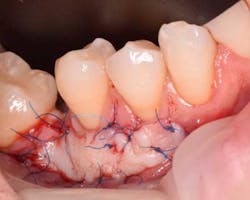

The free gingival graft was secured using 6.0 Prolene sutures in single interrupted fashion (figure 5). The gingival margin of the vestibular mucosa was fixed to the periosteum using the same suture. The donor site was sutured with 4.0 chromic gut resorbable sutures in single interrupted fashion (figure 6).